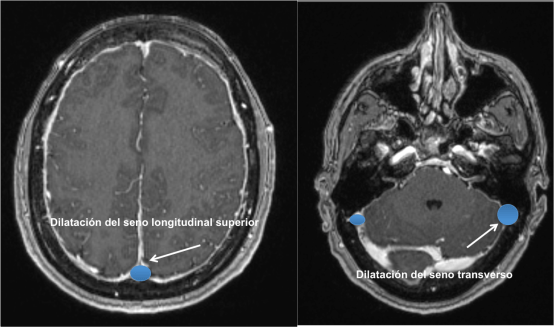

Según la hipótesis de Monro-Kellie cualquier variación del volumen de LCR debe ser compensado dado la naturaleza no compresible del cráneo. Como consecuencia, la pérdida de volumen de LCR se compensa con un aumento del volumen intracraneal y se produce una congestión venosa. Esta congestión venosa es visible en la Resonancia Cerebral y da lugar a una hipercaptación difusa meníngea.

En la Imagen 4 y 5 podemos ver el aspecto congestivo y redondeado de los senos venosos longitudinal y transverso.

En la Imagen 8, podéis observar el signo de distensión venosa descrito en casos de hipotensión intracraneal que se refiere a un cambio de la morfología del margen inferior de la porción media del seno transverso que adquiere una morfología convexa.